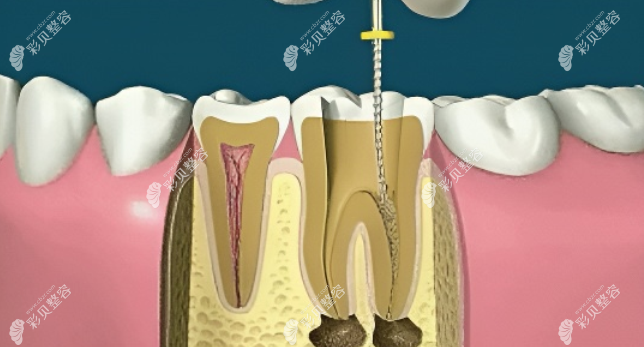

2、揭开髓腔

使用类似于钻的仪器,在牙齿上钻一个洞,并祛除里面的病毒组织。

3、确定根管工作长度

清除牙髓里的杂质后,参照X线照射结果,使用根管长度测量仪确定根管长度。

4、根管预备

根据上面得出的结果准备相对应的材料。

5、根管冲洗、消毒

根管冲洗的目的是清除牙髓内的微生物和细菌残渣,为根管充填提供一个比较好的生物环境。

6、根管充填

用根管充填剂和牙胶尖充填根管,从而达到严密封闭根管系统的功效。